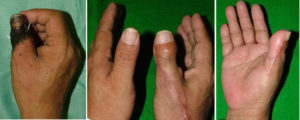

造母指手術

前医にて切断指再接着後壊死した症例に対して、Wrap around flapという手術を行い、母指を再建しました。

爪欠損の再建

小指指尖部切断に対して、第4足趾移植術を施行し、爪のある手指を再建しました。